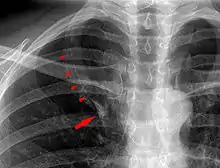

In human anatomy, an azygos lobe is a normal anatomical variation of the upper lobe of the right lung.[1] It is seen in 1% of the population. Embryologically, it arises from an anomalous lateral course of the azygos vein,[2] in a pleural septum within the apical segment of the right upper lobe or in other words an azygos lobe is formed when the right posterior cardinal vein, one of the precursors of the azygos vein, fails to migrate over the apex of the lung and penetrates it instead, carrying along two pleural layers that invaginates into the upper portion of the right upper lobe. As it has no bronchi, veins and arteries of its own or corresponding alteration in the segmental architecture of the lung, so it is not a true (misnomer), or even accessory, pulmonary lobe, but rather an anatomically separated part of the upper lobe.

An azygos lobe is usually an incidental finding on chest x-ray or CT scan, and is not associated with any morbidity.[3][4] However, it can cause technical problems in thoracoscopic procedures.[5]